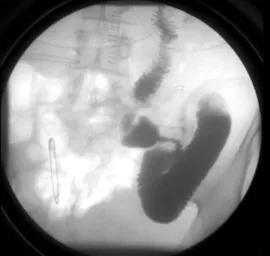

在术后我们给患者进行了上消化道造影检查,检查提示患者胃肠道功能恢复良好,胃肠蠕动可,并且没有吻合口漏的情况。患者在术后不久即恢复了进食进水,同时早期下地活动锻炼,到出院时身体状态已基本恢复。由于患者病理结果显示属于早期胃癌,后续只需规律复查,不需要进行化疗。而假如患者的术后病理分期提示为II期及以上,或合并有起他的高危因素,则还需要再进行术后的化疗。

复查消化道造影